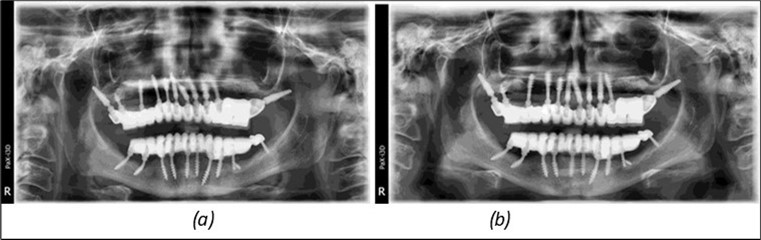

June 2022: Patient presented to our clinic for immediate-loading implant treatment At the time of presentation in 06. 2022, radiologically, advanced peri- implantitis is observed around the implants, with loss of native bone in the affected distal areas (Figure 1)

Figure 1.Panoramic overview picture before rehabilitation 06.2022

Figure 3.Panoramic pictures after removal of implants affected by peri-implantitis, extractions, alveolar crest regularization, and insertion of corticobasal and TPG implants (07.2022)

Figure 14.Rx panoramic final situation control: (a) Panoramic X-ray with the addition of a distal BCS implant in quadrant 3 at 11.2022; (b) Control X-ray, 10.2023.

The results of rehabilitation treatment with corticobasal and compressive implants with a polished surface after the failure of two stage implants were highlighted over a period of 3 years and 3 months as being very good (Figure 14, Figure 15), with the patient completing a satisfaction survey in this regard. Certainly, it is necessary to continuemonitoring these results in the long term.